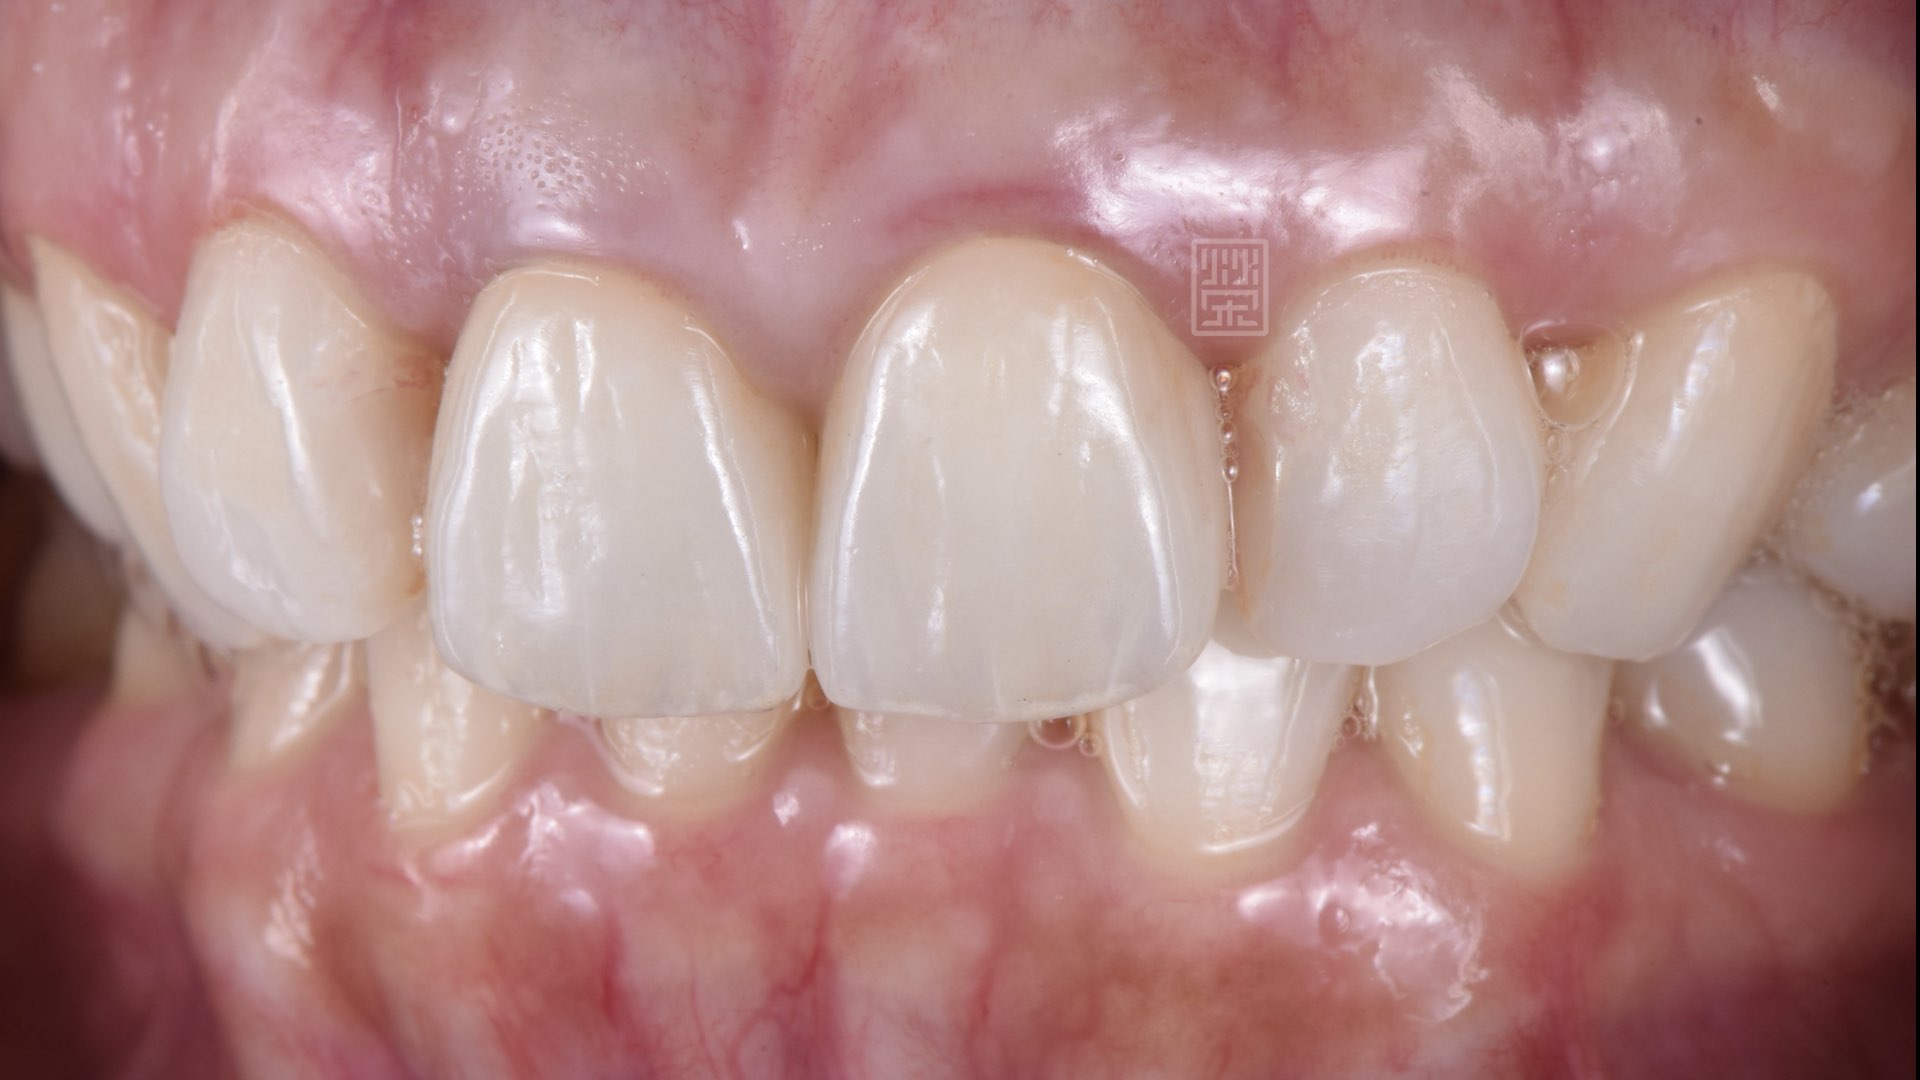

全瓷冠完成